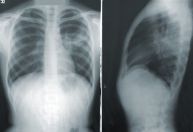

Uma pesquisa liderada pela Universidade de Oxford, na Inglaterra, com participação da Fiocruz e do Instituto Adolfo Lutz, sequenciou o genoma da tuberculose.

Foram coletadas mais de 15 mil amostras da bactéria que causa a doença e o resultado mostrou que mais da metade das cepas é resistente a pelo menos uma das drogas disponíveis para tratamento.